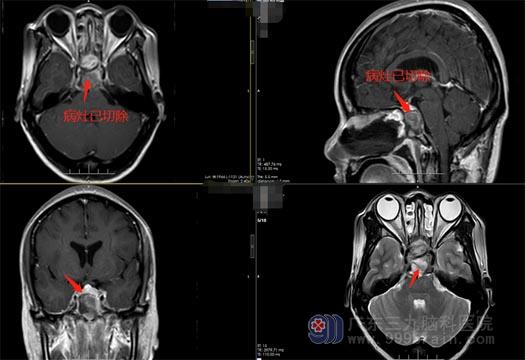

病因明确,该病变为良性病变,保守治疗基本无效。完善检查后,经过神经外五科治疗团队缜密的术前讨论,选择以创伤性小、费用少、康复快的手术方案,为黄阿姨选择了在全麻下经鼻切除肿瘤。术中见外展神经位于肿瘤下方,小心翼翼地将肿瘤分离、全切,手术过程顺利。

术后第二天,黄阿姨的右眼球就可以慢慢往外转了,不日就能出院。